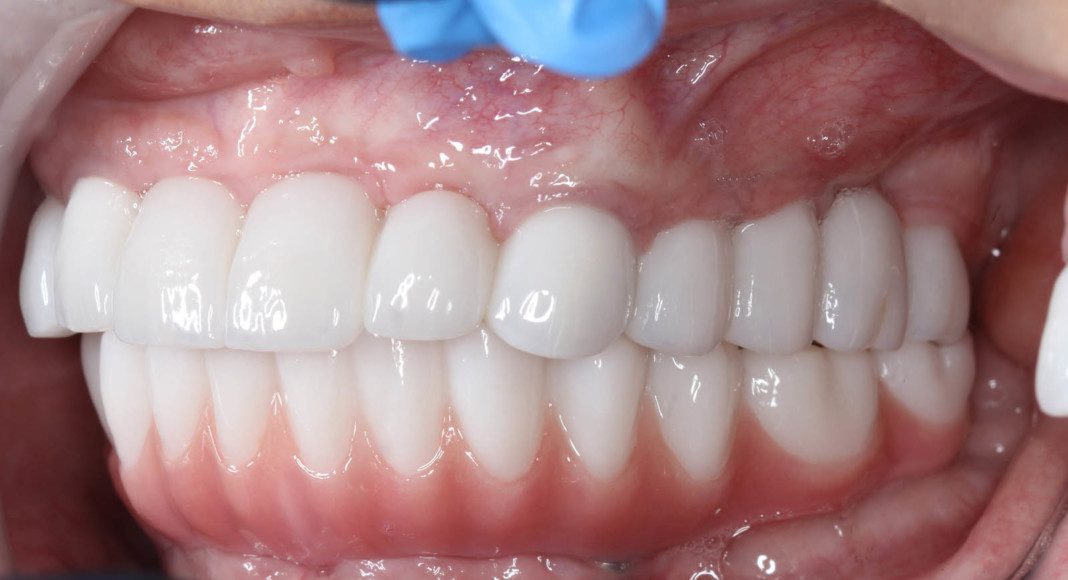

Right lateral, mirror view of the upper and lower zirconia bridges. Note the beautiful, healthy tissue response.